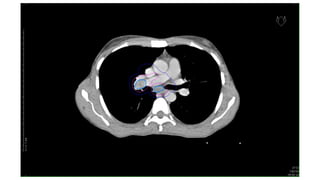

NSCLC

CT images ofCa Lungs